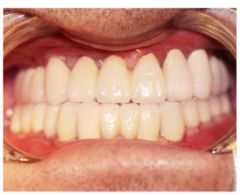

种植修复后照片

这一位老先生则选择了All-on-4种植技术,即拔即种,上下颌分别种植4个植体就完成了全口牙齿修复,费用降低了不少,而且创伤小,恢复快。